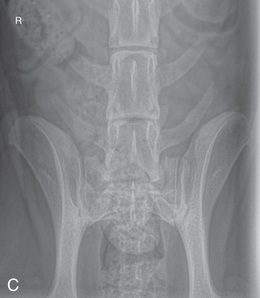

MEASURE: Level of L1.

CENTRAL RAY: Level of L4 (palpate).

BORDERS: T12 to S1 (Just cranial to both the origin of the last rib and acetabulum).

MEASURE: Level of the lumbosacral junction or the highest point of the wings of the ilia.

CENTRAL RAY: Level of the lumbosacral junction (just caudal to the wings of the ilia).

BORDERS: L4 to the most cranial caudal vertebra (just cranial to the wings of the ilia to the femoral head).

MEASURE: Wings of the ilia.

CENTRAL RAY: On the lumbosacral junction, caudal to the wings of the ilia, at an angle of 20 to 30 degrees in a caudocranial direction.

BORDERS: L4 to the most cranial-caudal vertebra (from just cranial to the wings of the ilia to the femoral head).